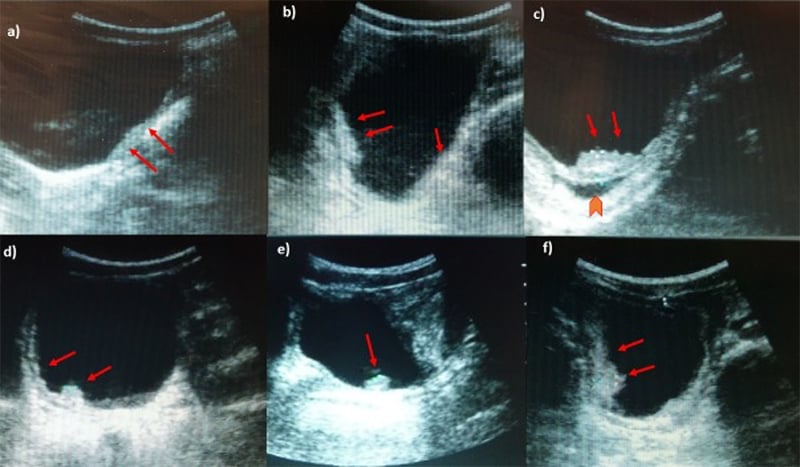

Figure 48. Ultrasonography images of urinary bladder of [School-Aged Children] infected with S. haematobium. a) Thickening of the bladder wall, transverse plane shows thickening of the left lateral wall (arrows); b) Diffuse thickening of the bladder wall more evident in the right posterior wall, echogenic snow in the lumen; c) In oblique longitudinal plane, ultrasound image shows a mass-like lesion in the mucosa layer of the bladder. Block arrow indicates the dilation of the ureter; d) longitudinal plane shows a marked and diffuse thickening of the bladder wall with a mass-like lesion (arrow); e) Mass-like lesion in the absence of a marked and diffuse thickening of the bladder wall; f) Multifocal thickening of the wall, particularly evident on the right and posterior wall. (Reproduced with permission, PLOS https://doi.org/10.1371/journal.pntd.0005400.g003 )